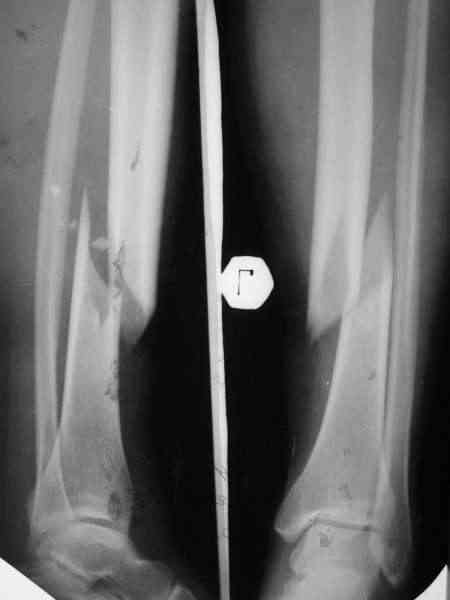

На неделе встретилась пациентка, которой выполнил около 1,5 лет назад остеосинтез голени по поводу закрытого винтообразного перелома н/3 б/берцовой кости и в/3 м/берцовой кости со смещением.

По ряду причин пришлось применить следующий метод (см. вложение).

В приватной беседе с коллегой было высказано мнение, что данный подход к лечению таких переломов дискредитирует как методику остеосинтеза по Илизарову, так и погружной остеосинтез по АО. Дискуссия дошла до того, что я к концу уже почти уверовал, что перелом сросся не благодаря, а вопреки лечению. Такой же остеосинтез с открытой репозицией, фиксацией позиционным винтом и шинированием в аппарате Илизарова было выполнено еще одной пациентке. Исход - аналогичный.